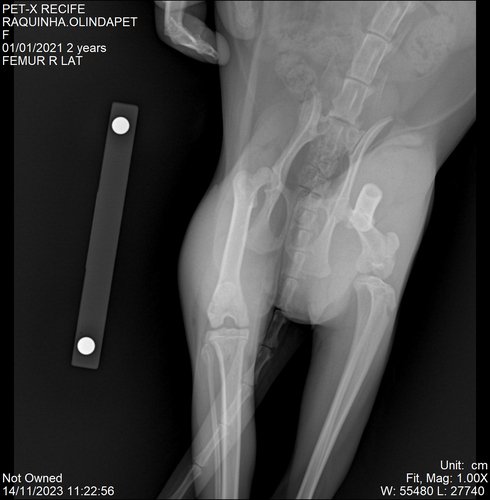

Raquinha, como é carinhosamente chamada pela família e amigos, fraturou o fêmur e precisará de cirurgia para evitar perder os movimentos da pata traseira. O que impede ela de andar, pular, brincar e fazendo com que ela se limite a se alimentar e fazer suas necessidades.

Seguem as receitas, laudo, pedidos de exames o raio - x da fratura de fêmur: